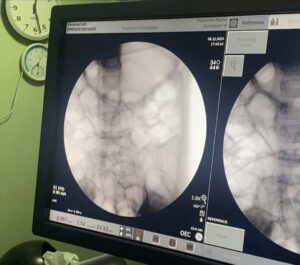

أوضح البيان أنه على الفور جرى حجز الحالة بالمستشفى، وجرى عمل اللازم من إشاعات وتحاليل وجرى تشخيص الحالة بوجود جسم غريب داخل المعدة وعلى الفور جرى دخول الطفلة إلى غرفة العمليات.

وجرى استخراج قطعة معدنية حادة من برايه القلم الرصاص من جدار المعدة باستخدام منظار الجهاز الهضمي وقام الأهل بتوجيه كل الشكر والعرفان للفريق الطبي وكل من تعاون في إنقاذ حياة طفلتهم.